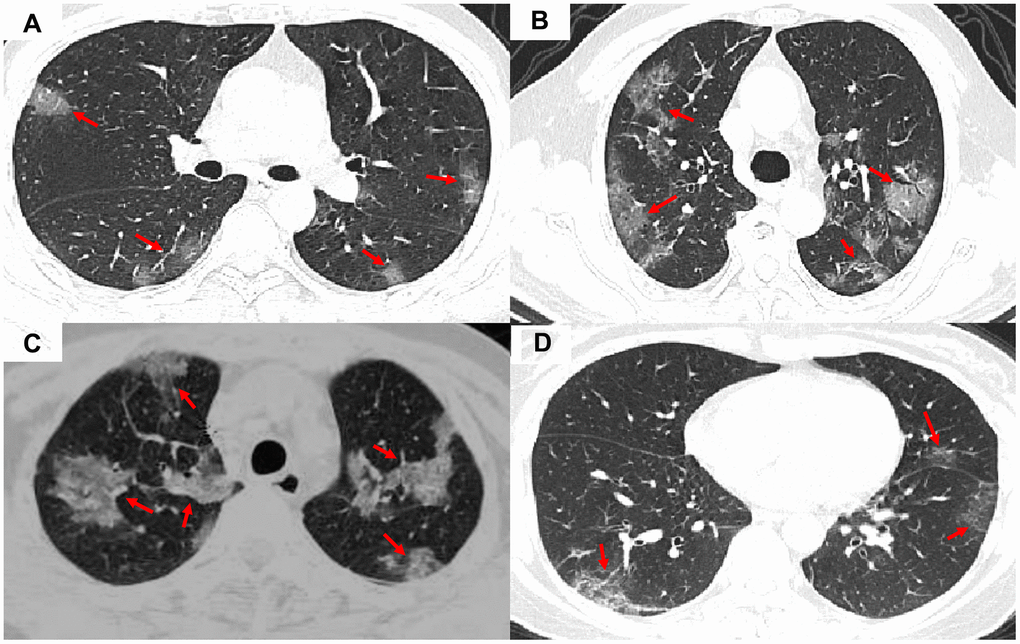

The clinical characteristics of patient data used are shown in Table 1. The COVID-19 patients had significantly higher lesion numbers, CK-MB activity, LDH activity, and bilateral, peripheral, or mixed central and peripheral pulmonary distribution than the non-COVID-19 viral-induced pneumonia patients. Most of the symptoms, laboratory results, and CT manifestations had no significant differences between COVID-19 and non-COVID-19 patients (Table 1). Representative images of COVID-19 pneumonia, adenovirus pneumonia, cytomegalovirus pneumonia, and influenza virus pneumonia are shown in Figure 1.

Figure 1. Representative images of COVID-19 pneumonia, adenovirus pneumonia, cytomegalovirus pneumonia, and influenza virus pneumonia. (A) A transverse CT image from a 35-year-old man with adenovirus pneumonia showing bilateral ground-glass opacities in the upper lobes with a rounded morphology (arrows). (B) COVID-19: A transverse CT image from a 57-year-old man with COVID-19 showing more limited ground-glass opacities in the bilateral upper lobes with an elliptical morphology (arrows). (C) A transverse CT image obtained in a 45-year-old female with cytomegalovirus pneumonia showing bilateral ground-glass and burr-like, denser, and less transparent distribution (arrows). (D) A transverse CT image of a 61-year-old man diagnosed with influenza virus pneumonia showing bilateral ground-glass opacities in the upper lobes (arrows).